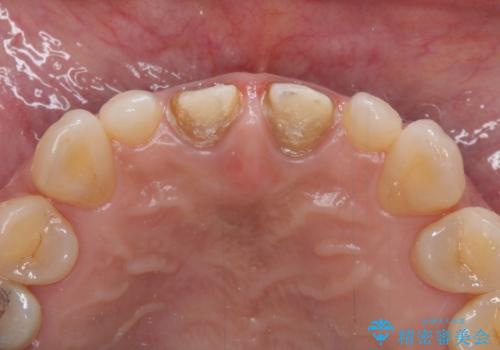

前歯をメタルフリーに 根管治療で不安を取り除いてから

セラミック治療と根管治療を行いました。

金属を使用したメタルボンドクラウンが入っていたため、いつかオールセラミックにしたいときに根管治療も行ったほうが良いとご提案し、今回行いました。

歯と歯肉の境目の色は、歯自体が黒くなっている場合、完全にカバーすることは難しいです。

根管治療について

保険根管治療は回数がかかることが多く、終了予定がわかりにくいです。

当院では、根管治療は長い時間のご予約を頂き、多くの場合2~3回で終わります。

根管治療は歯内の治療なので患者様には見えない場所ですが、ここが細菌で汚染されると激しい痛みや長引く違和感の原因になります。

当院では、清潔な治療を徹底し、顕微鏡を使用した精密な治療を行っています。